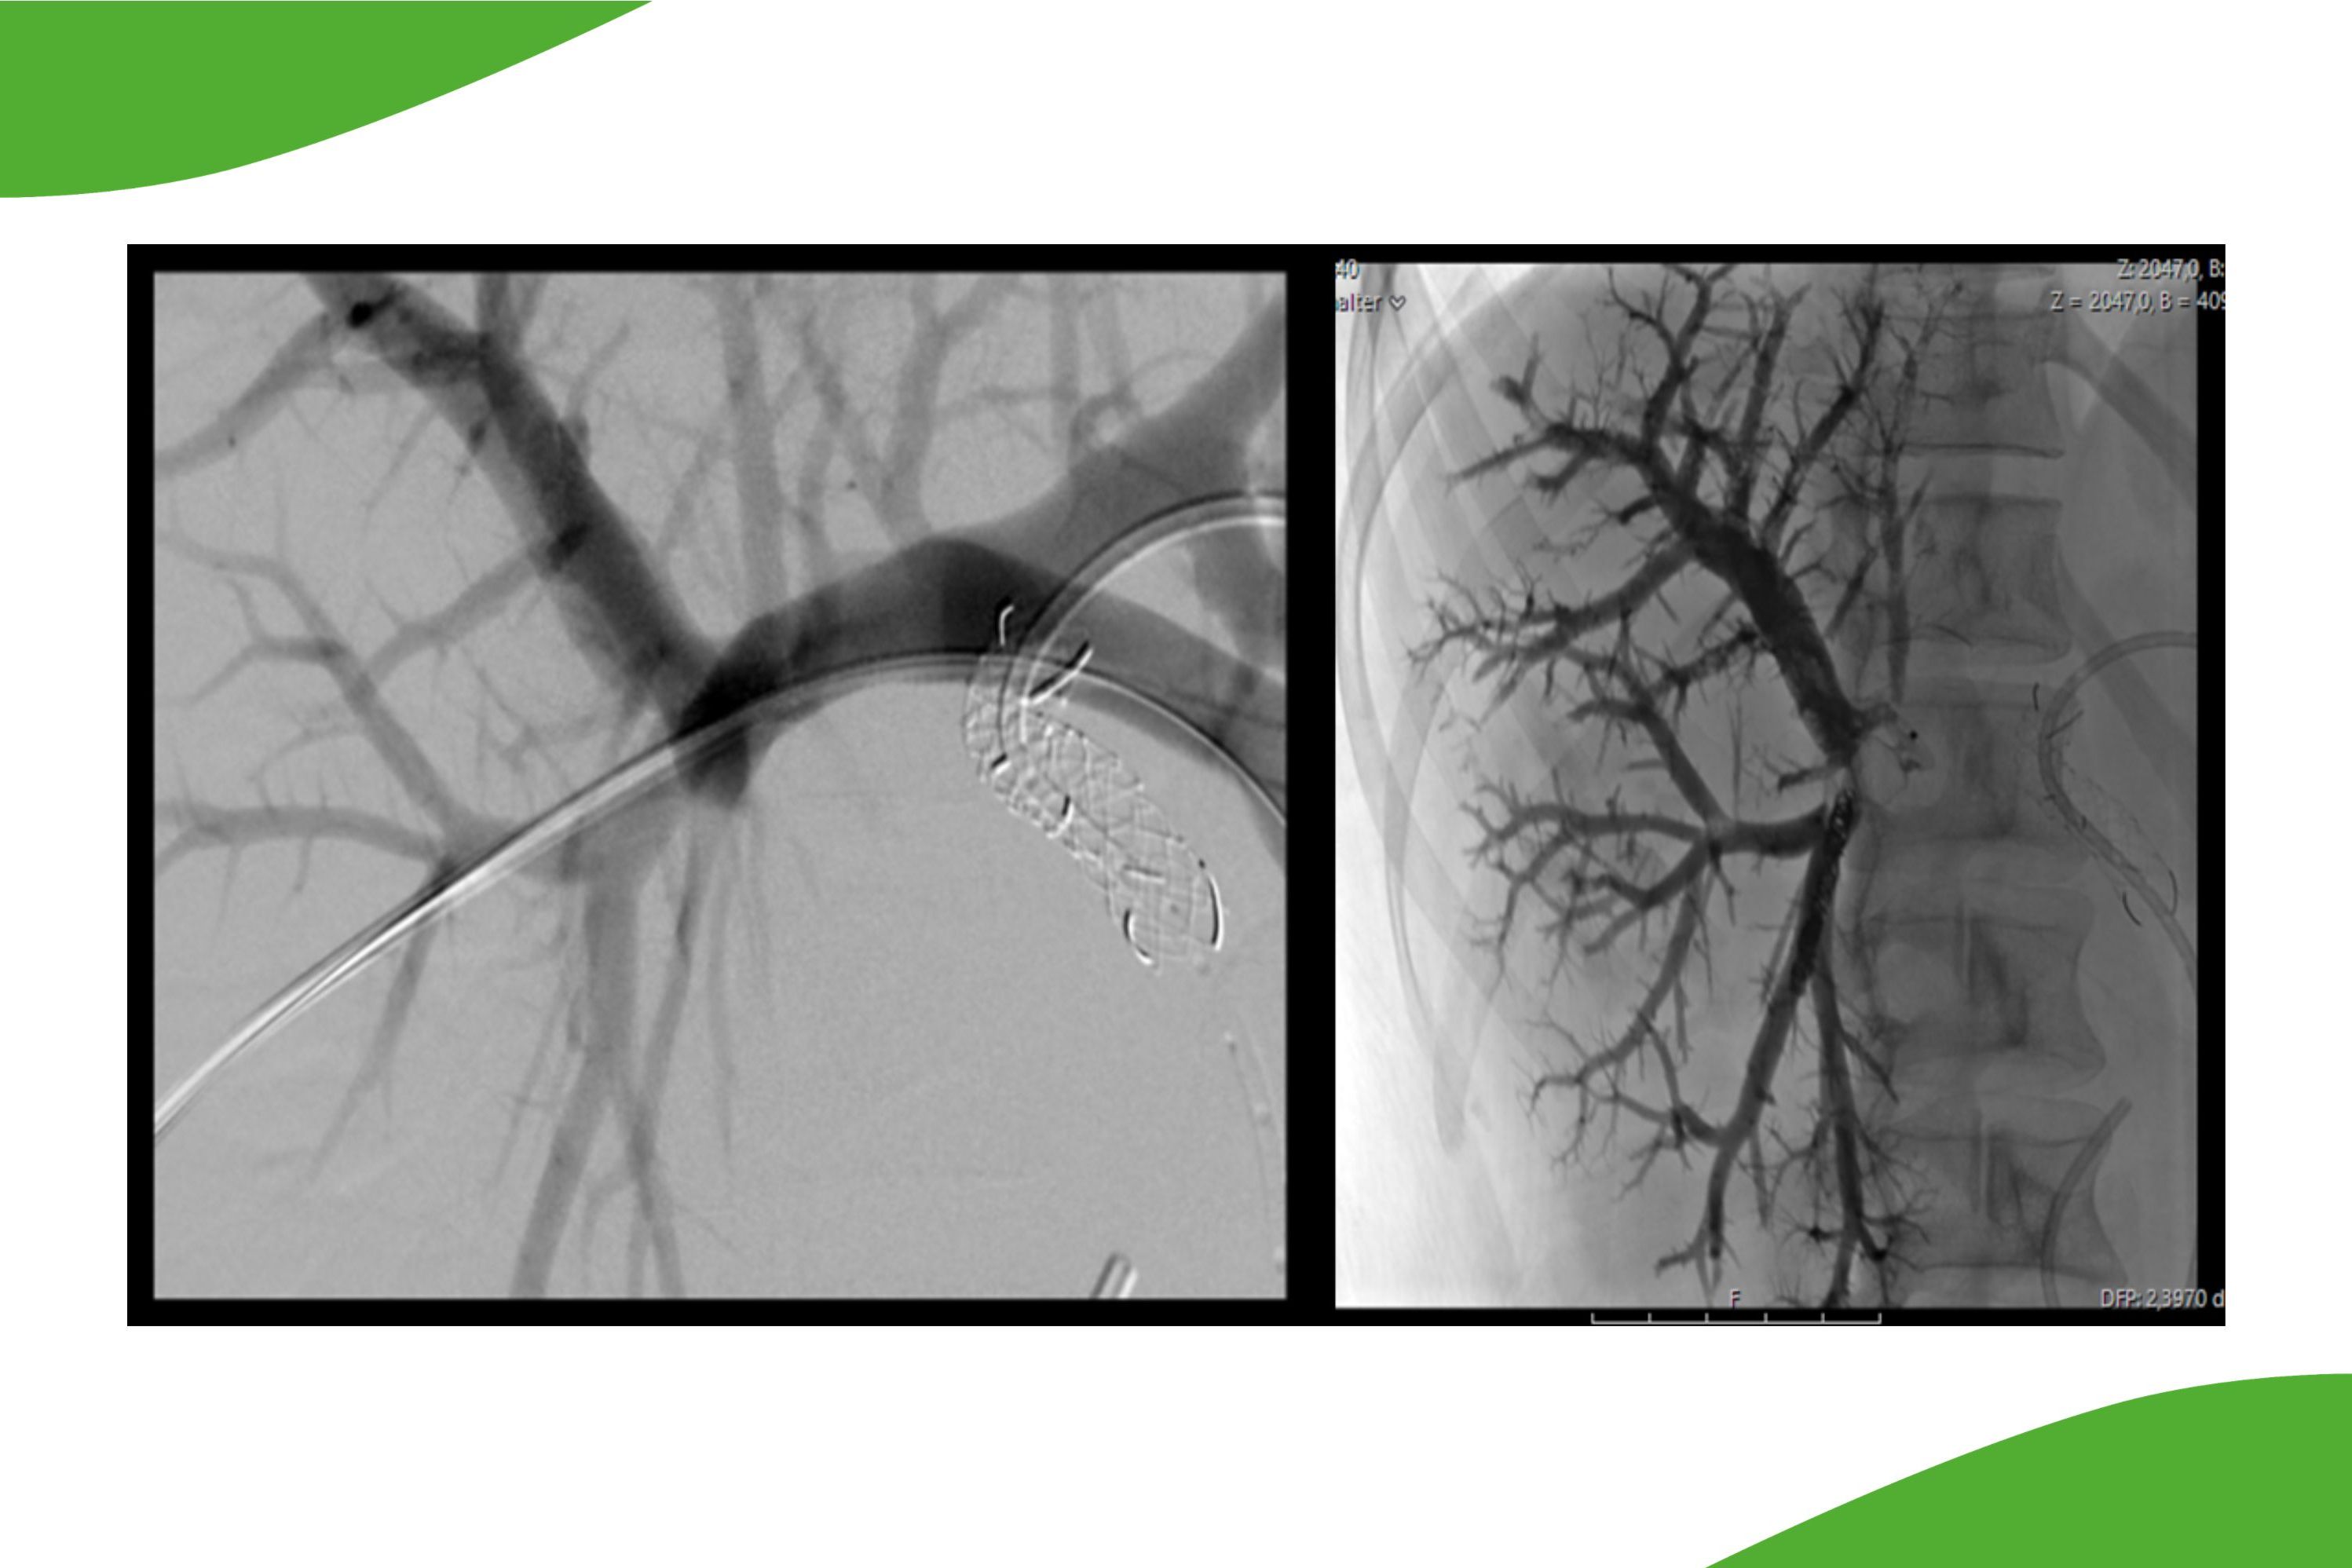

Durch Einsatz von sehr kleinlumigen Kathetersystemen ist heutzutage auch die Behandlung der kleineren Unterschenkelgefäße bis auf Höhe des Fußrückens möglich. Insbesondere bei Patienten mit drohender Fußamputation kann hier durch eine Rekanalisation der Unterschenkelgefäße eine verbesserte Durchblutungssituation erreicht werden, um eine Fußamputation möglichst zu vermeiden. Für eine solche Behandlung sind spezielle dünnlumige und langstreckige Ballonkatheter erforderlich. Am Klinikum Saarbrücken wird in Zusammenarbeit mit den Kollegen der Gefäßchirurgie regelmäßig auch die Rekanalisation von Unterschenkelgefäßen durchgeführt. Dabei kann es auch erforderlich sein, nicht nur ‚von oben‘, also entlang des Blutstroms vorzugehen, sondern wir sind mittlerweile auch in der Lage, vom Fußrücken rückwärts gerichtet sogar langstreckig vollständige Verschlüsse zu behandeln.

Ob eine interventionelle Behandlung (Ballondilatation) im Unterschenkelbereich eine Behandlungsoption darstellt, oder aber ob eine operative Sanierung mit Bypass der Vorzug gegeben werden soll, wird jeweils mit den Kollegen der Gefäßchirurgie interdisziplinär abgesprochen. Letztendlich ist aber durch diese Verfahren häufig ein Fußerhalt bzw Beinerhalt möglich.

Grafische Darstellung der Unterschenkelgefäße: Die Abbildungen zeigen links die Gefäßverschlüsse sowie rechts nach perkutaner transluminaler Angioplastie (PTA) und Stentimplantation. Nach dem Eingriff ist die Gefäßausstrombahn wiederhergestellt.